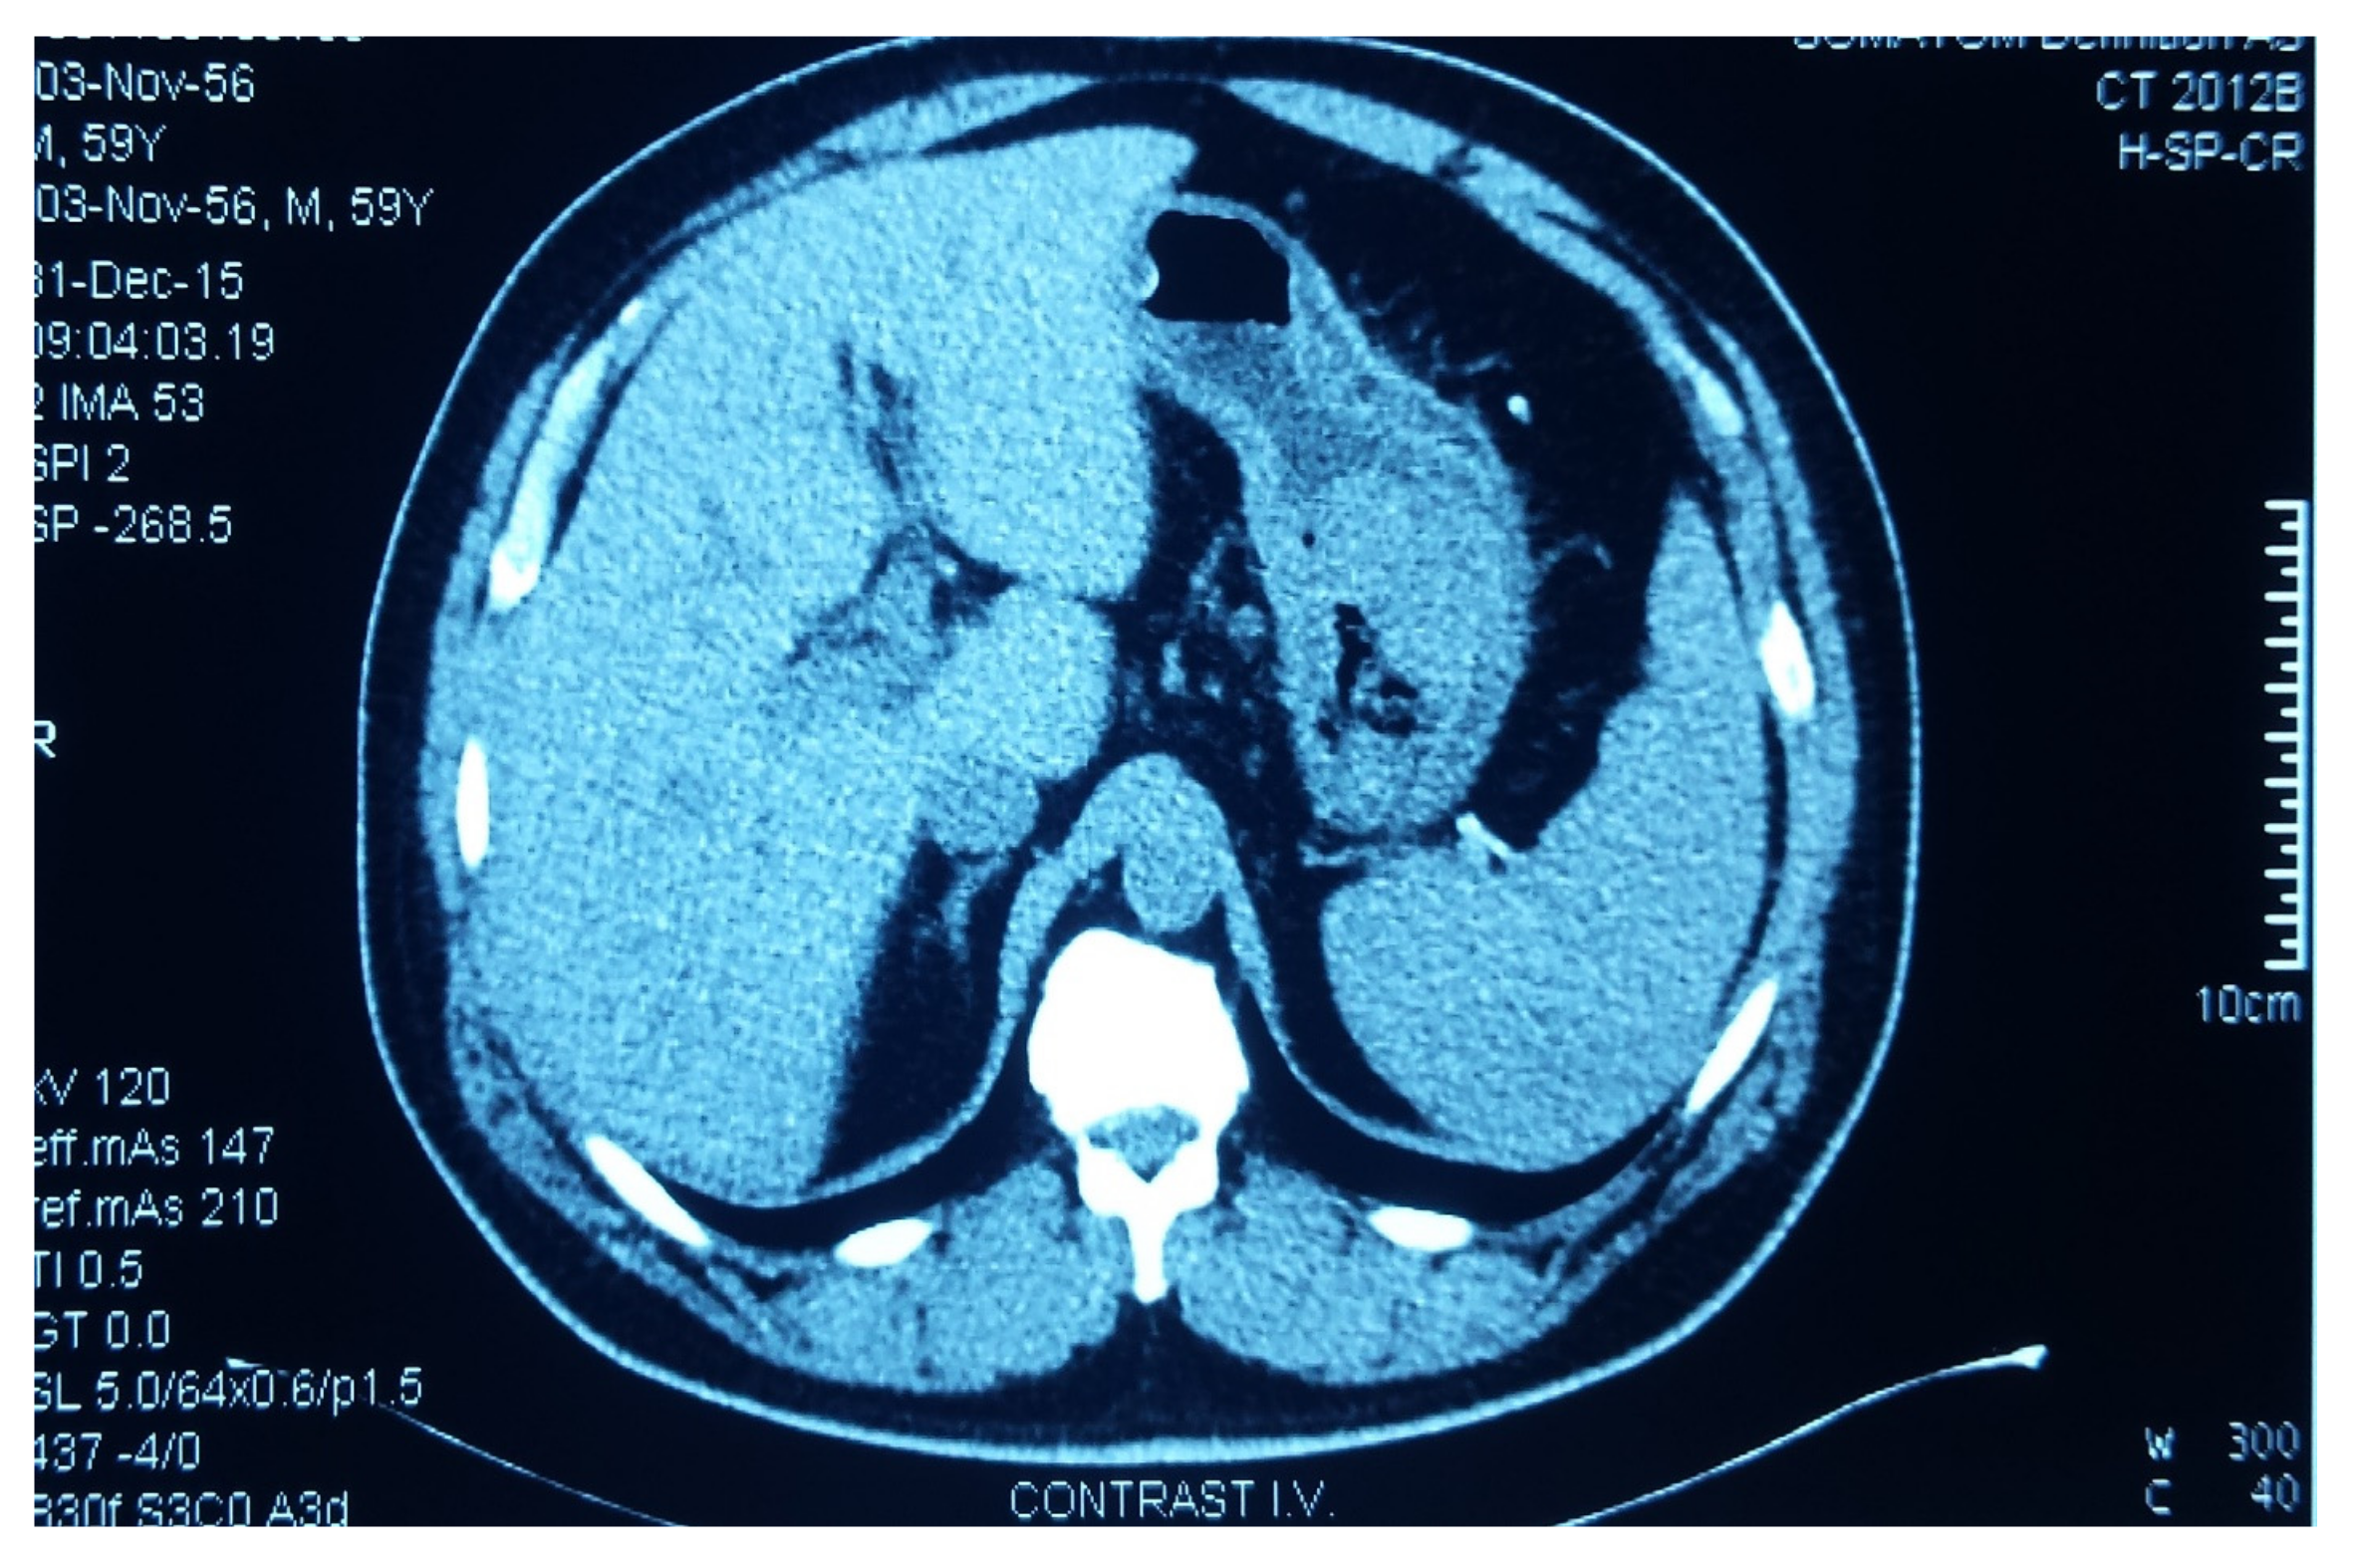

We present the case of a 61-year-old insulin-requiring diabetic patient with chronic C viral hepatitis, type II aorto-iliac peripheral artery disease with chronic stage II ischemia of both legs with anemia and hypovolemia who presented with a massive upper gastrointestinal tract (GIT) bleeding due to a hemorrhagic gastric adenocarcinoma. An urgent CT (computerized tomography) was performed, showing the gastric tumor (Figure 1). Based on the critical status of the initial presentation, the patient was taken to theater in emergency, where a total gastrectomy was performed (esophago-jejune-anastomosis, Omega shaped with Brown anastomosis at the tip of the jejunal loop) and the gastric adenocarcinoma surgical specimen was removed (Figure 2). After the gastrectomy procedure, the patient was closely monitored. Given the favorable evolution and lack of post-operative complications, the patient was discharged.

Figure 1. Computer Tomography (CT) scan showing the gastric tumor.